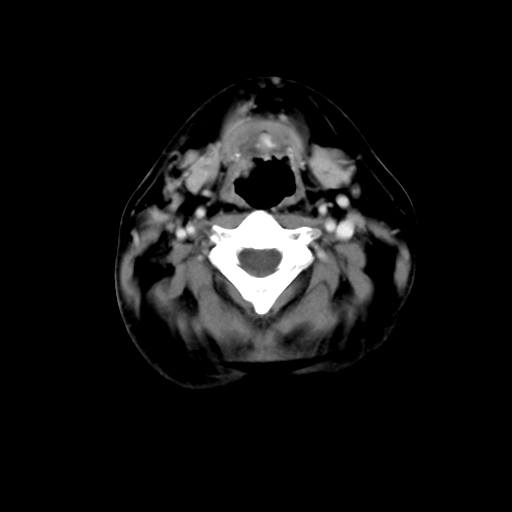

标题: CT24019:男,45岁,发现颈部肿物5个月。 [打印本页]

男,45岁,发现颈部肿物5个月,彩超示:双侧颈部及下颌部软组织增厚。

脂肪瘤。

考虑双侧颈项部良性对称性脂肪增多症。